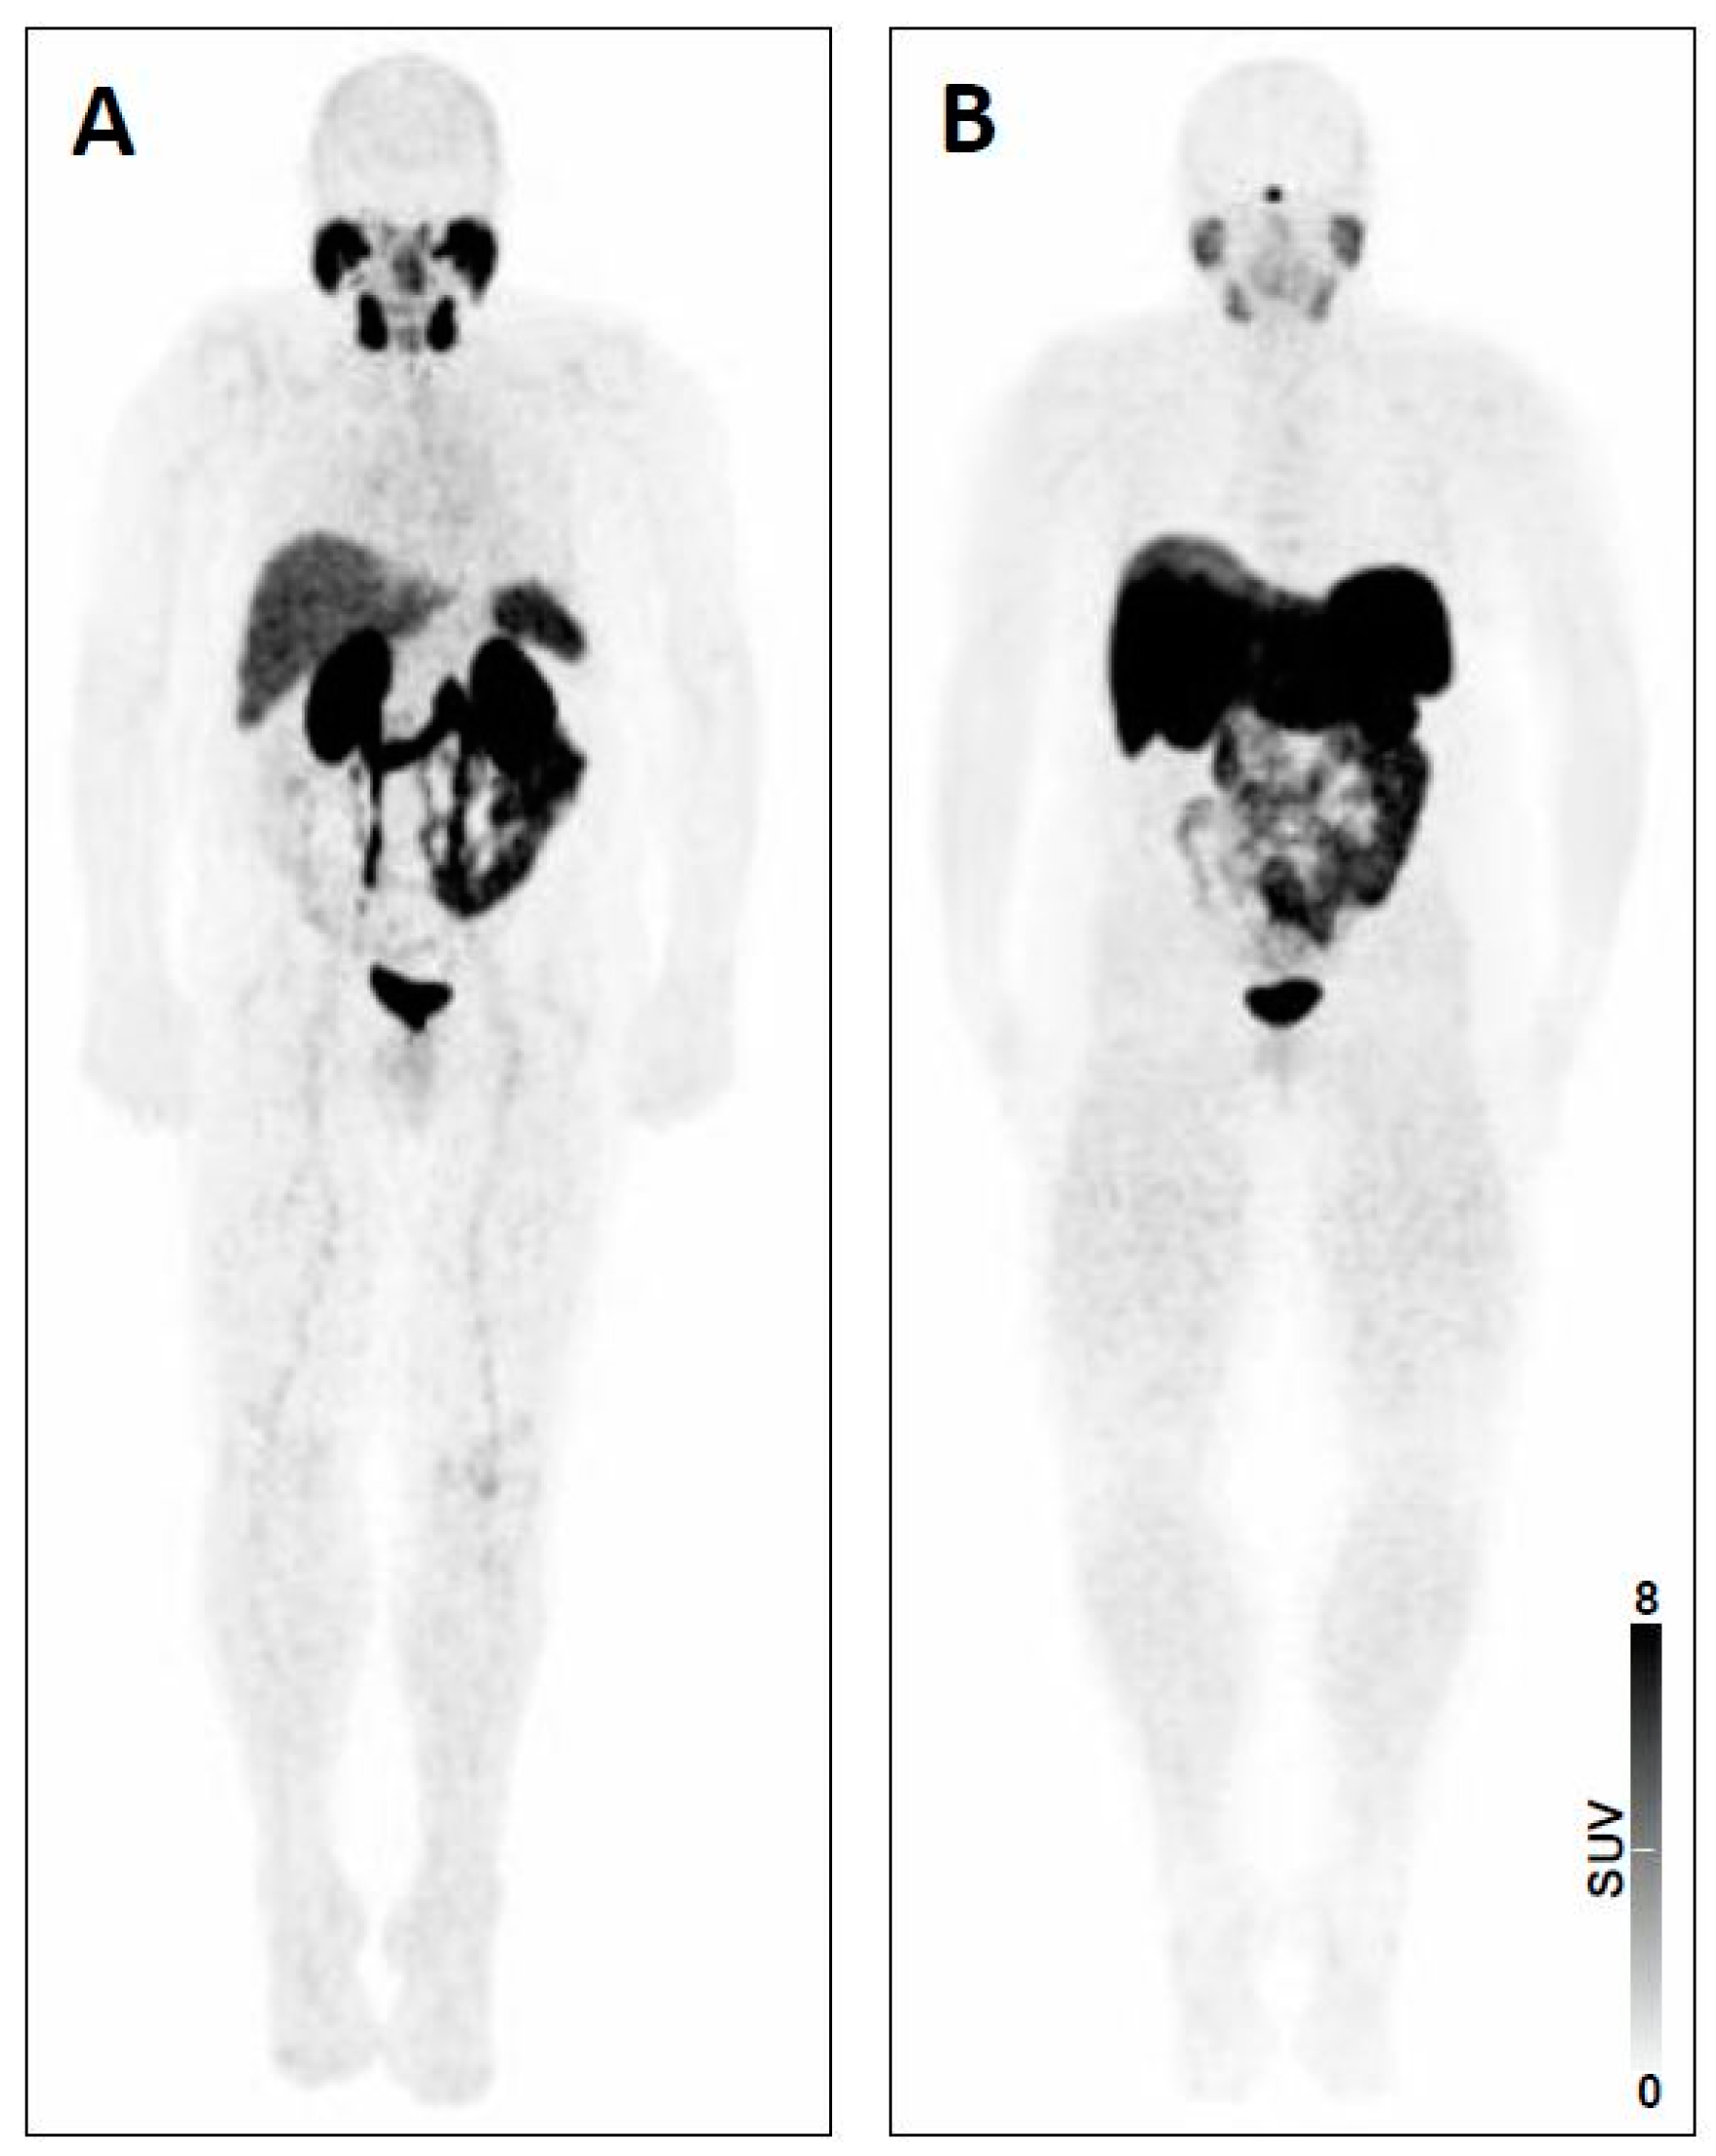

- Cherk, M.H.; Kong, G.; Hicks, R.J.; Hofmann, M.S. Changes in biodistribution on 68 Ga-DOTA-Octreotate PET/CT after long acting somatostatin analogue therapy in neuroendocrine tumour patients may result in pseudoprogression. Cancer Imaging 2018. [Google Scholar] [CrossRef]

- Beauregard, J.M.; Hofman, M.S.; Kong, G.; Hicks, R.J. The tumour sink effect on the biodistribution of 68Ga-DOTA-octreotate: Implications for peptide receptor radionuclide therapy. Eur. J. Nucl. Med. Mol. Imaging 2012, 39, 50–56. [Google Scholar] [CrossRef] [PubMed]

- Werner, R.A.; Hanscheid, H.; Leal, J.P.; Javadi, M.S.; Higuchi, T.; Lodge, M.A.; Buck, A.K.; Pomper, M.G.; Lapa, C.; Rowe, S.P. Impact of tumor burden on quantitative [(68)Ga] DOTATOC biodistribution. Mol. Imaging Biol. 2018. [Google Scholar] [CrossRef]